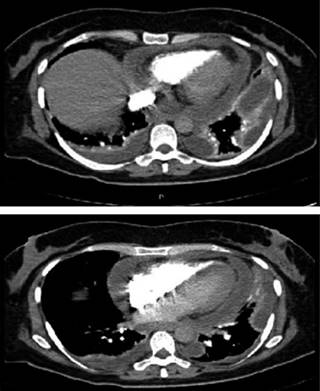

Mujer de 50 años, originaria de Cuernavaca, estado de Morelos, de ocupación campesina. Antecedentes de infección de vías aéreas de repetición. Inicia padecimiento actual dos meses previos a su ingreso con disnea progresiva, tos seca, dolor precordial y rinorrea con tratamientos múltiples no especificados sin mejoría. Dos semanas previas a su ingreso presenta además ortopnea y edema de miembros inferiores, debido a ello es referida al Instituto Nacional de Enfermedades Respiratorias Ismael Cosío Villegas de la Ciudad de México. A su ingreso los signos vitales eran TA 110/70 mmHg, FC 98 X’, FR 28 X’, temperatura 36.8 oC, saturación 90%. Campos pulmonares con hipoventilación basal bilateral y ruidos cardíacos disminuidos en intensidad. Se realizó radiografía de tórax encontrando datos de cardiomegalia y derrame pleural bilateral (Figura 1), se hace tomografía contrastada de tórax, donde se observa derrame pericárdico y derrame pleural bilateral (Figura 2). Ecocardiograma con pericardio engrosado de 9 mm e hiperrefringente con derrame de 500 cm3, colapso parcial de cavidades derechas y alternancia eléctrica en el electrocardiograma con variación en el llenado mitral > 35%. Debido a que no se contaba con diagnóstico etiológico al momento, se decidió realizar toracoscopia derecha diagnóstica con ventana pericárdica. Debido a los hallazgos quirúrgicos de líquido pericárdico purulento de 600 mL, no fétido (Figura 3) con adherencias firmes de pericardio a miocardio en algunos segmentos, pulmón y pleura y derrame pleural cetrino de 300 mL, se decidió convertir a toracotomía posterolateral y realizar pericardiectomía parcial para adecuado lavado, drenaje y desbridamiento de tejido necrótico y fibrina (Figura 4). Los cultivos de líquido pericárdico y biopsia de pericardio fueron negativos. No se hizo estudio citoquímico de líquido pericárdico debido a sus características purulentas. Los estudios para tuberculosis en biopsia y líquido pericárdico tinción Ziehl-Neelsen, baciloscopia y una prueba rápida de reacción en cadena de la polimerasa y de resistencia a rifampicina (GeneXpert MTB/RIF)MR para formas extrapulmonares de la tuberculosis fueron negativos. El galactomanano también fue negativo. Reporte de patología de pericardio resecado: pericarditis fibrinosa no granulomatosa con datos histológicos que sugieren etiología fímica, sin datos de malignidad. Ante la negatividad de todos los estudios se realizó inmunodifusión de histoplasma en orina (antigenuria), que resultó positiva. Posterior a estos estudios se indicó tratamiento con anfotericina B por el servicio de infectología durante tres semanas, después de lo cual se tomó control de antígenos en orina, los cuales fueron negativos y se decidió suspender tratamiento. Mostró evolución con mejoría clínica. Tomografía contrastada de control para delimitación de estructuras cardíacas sin datos de derrame pericárdico y escaso derrame pleural derecho (Figura 5). Fue egresada del instituto con seguimiento al mes, con adecuada evolución sin recaídas al momento. Debido a la pandemia se dio seguimiento por vía telefónica con adecuada evolución a los tres meses.